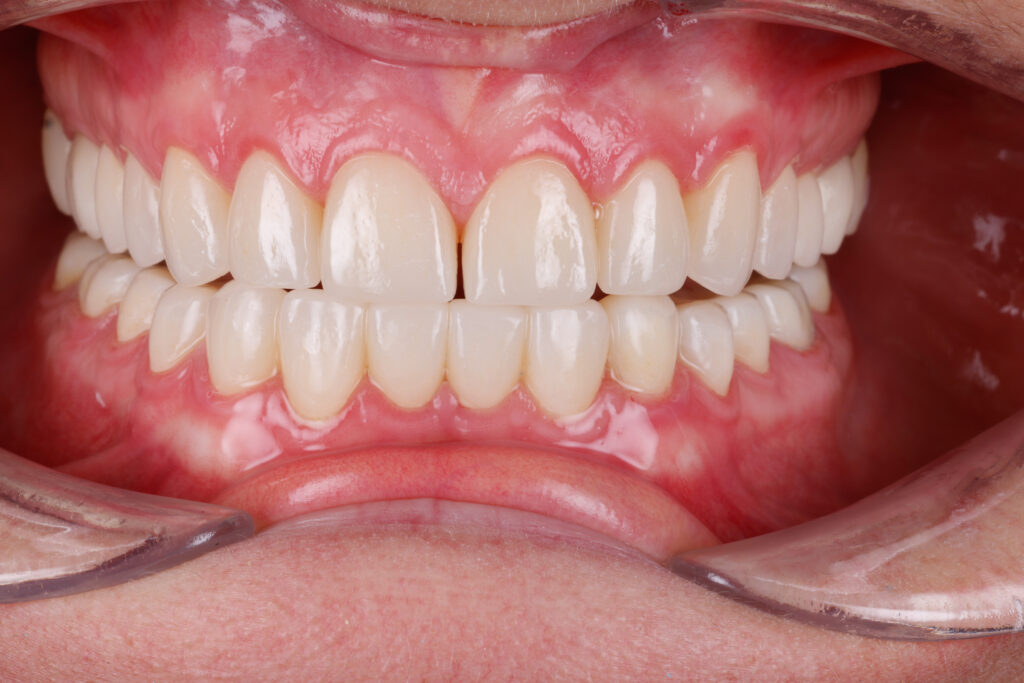

Before

After